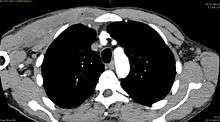

| Transverse T2 magnetic resonance imaging section through the hip region showing abscess collection in a patient with pyomyositis. | |